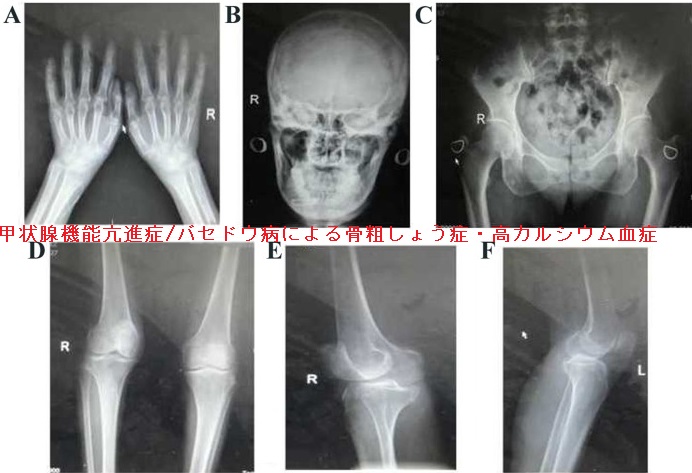

甲状腺機能亢進症/バセドウ病による骨粗しょう症・高カルシウム血症

甲状腺機能亢進症/バセドウ病患者は、過剰な甲状腺ホルモンの影響で骨が分解され、骨粗しょう症になっている可能性があります(高代謝回転型骨粗鬆症)(Indian J Med Res. 2012 Mar;135(3):277-86.)。

単に骨量が減るだけでなく、骨の微細構造が損なわれ骨強度も低下、脆い骨になります[Thyroid. 2021 Feb;31(2):208-216.]。

また、甲状腺機能亢進症における骨代謝分解の亢進で、骨から溶け出したカルシウムによる高カルシウム血症がおきる場合があります。頻度は10-20%とされます(Ann Intern Med. 1966 Sep; 65(3):429-42.)。